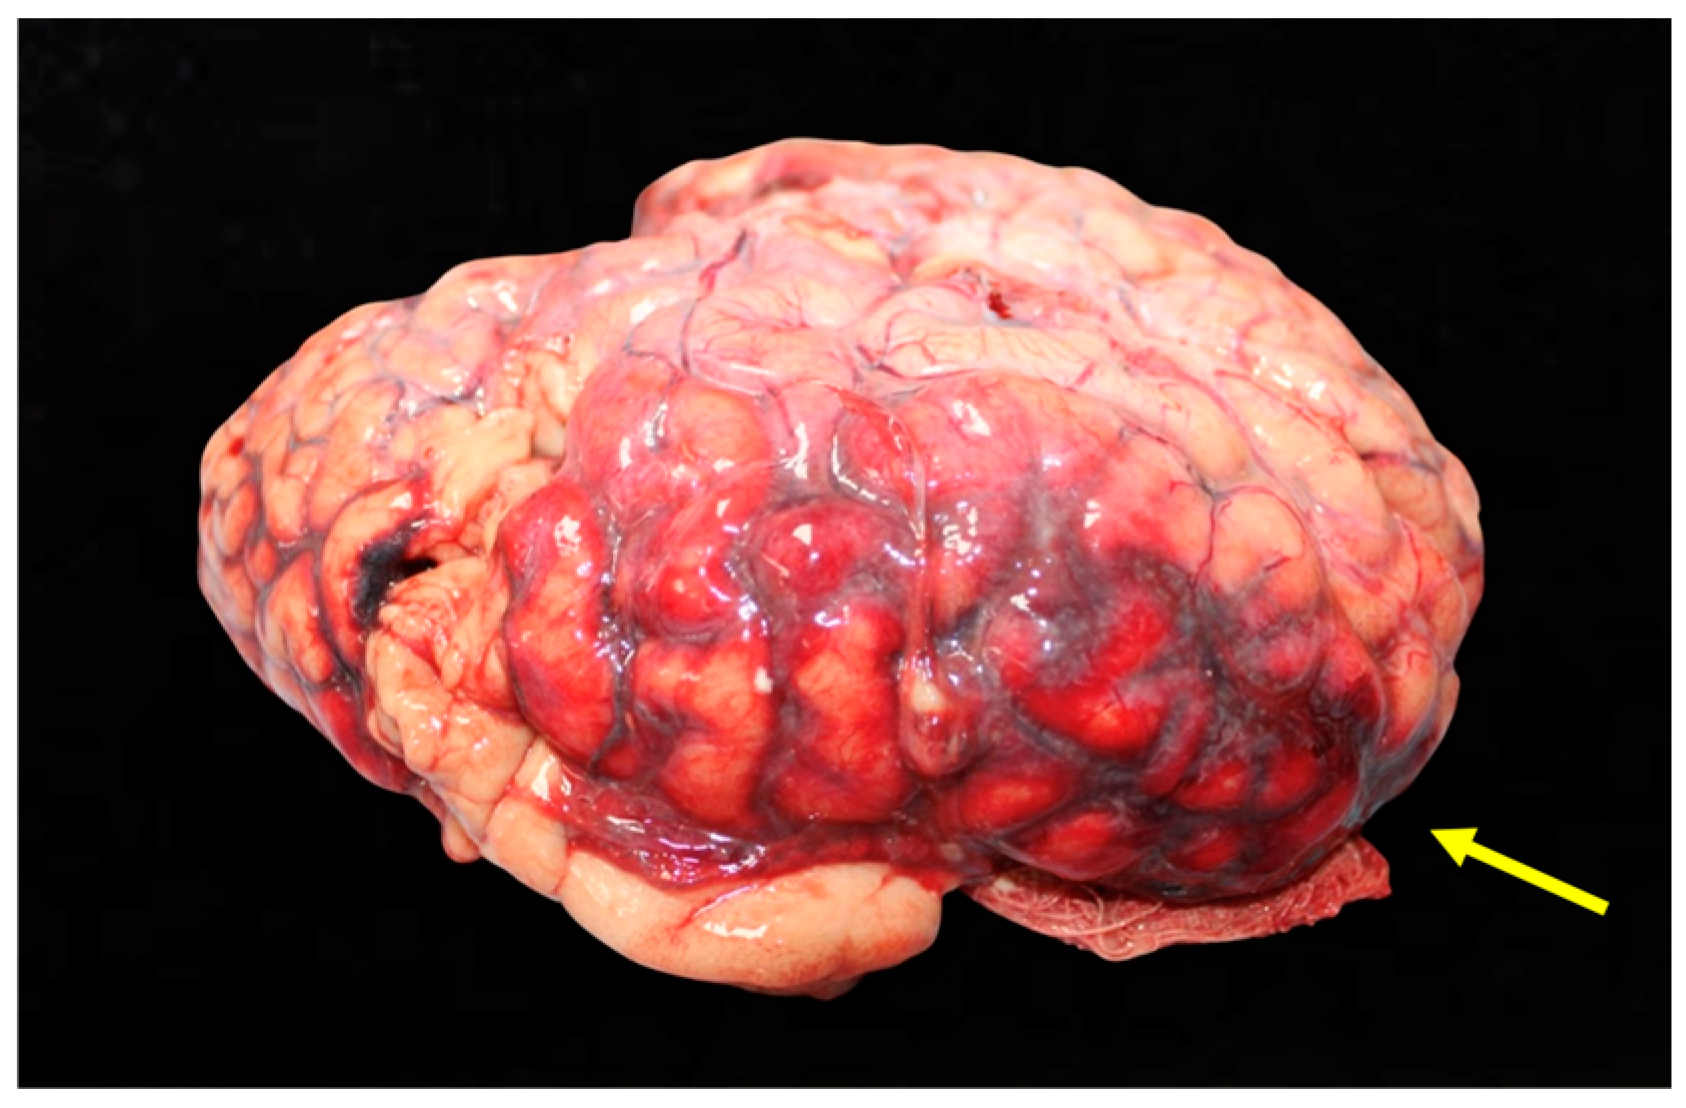

Figure 4. Detailed view of the bleeding into the subarachnoid space, with clear demarcation of the hemorrhage.